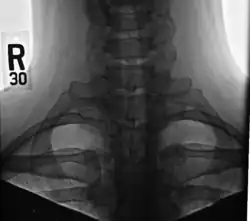

A cervical rib in humans is an extra rib which arises from the seventh cervical vertebra. Their presence is a congenital abnormality located above the normal first rib. A cervical rib is estimated to occur in 0.2%[7] to 0.5%[8] (1 in 200 to 500) of the population.[9] People may have a cervical rib on the right, left or both sides.[10][11]

Most cases of cervical ribs are not clinically relevant and do not have symptoms;[12][13] cervical ribs are generally discovered incidentally, most often during x-rays and CT scans.[8][9][11] However, they vary widely in size and shape,[8] and in rare cases, they may cause problems such as contributing to thoracic outlet syndrome,[12] because they press on the nerves.[12][14]

On imaging, cervical ribs can be distinguished because their transverse processes are directed inferolaterally, whereas those of the adjacent thoracic spine are directed anterolaterally.[16]